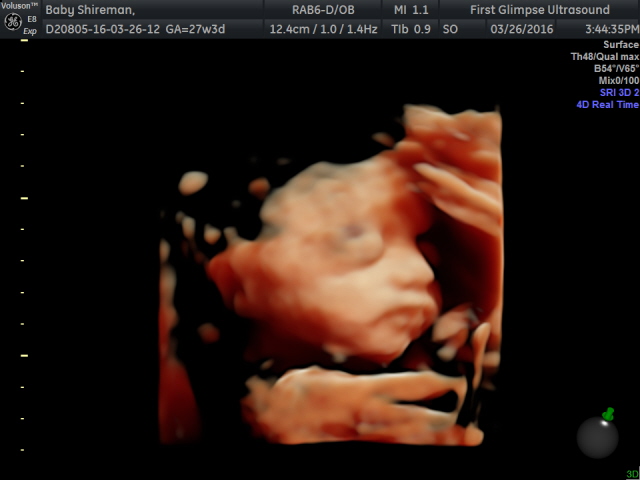

We had our 3rd 3d Ultrasound today because baby girl was being stubborn and didn't want us to see her face lol.... Well today she gave in and gave us some great shots!!. We saw arms and hands and feet, her mouth opening and closing, she was holding on to her feet and playing around! So fun and exciting to get a peak at our baby girl!

| Shes holding her foot!! You can see her little thumb on the left side and fingers to the right! |

| Opening and closing her mouth! |